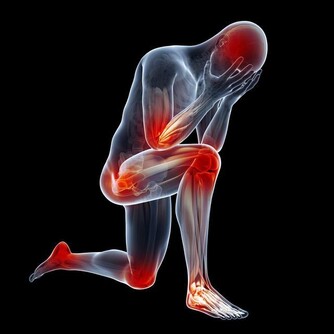

一、心絞痛

簡單地說,心絞痛是冠狀動脈供血不足,心肌急劇的、一過性的缺血缺氧,繼之引起胸痛或胸部嚴重不適。

心絞痛是冠心病的一種表現形式。其典型特點為陣發性前胸壓榨性或絞榨樣疼痛感覺,

主要位於胸骨後部或左前胸,可放射至頸部或左上肢。

更為嚴重的患者還有瀕死樣感覺,每次發作的時間約為數分鐘至十幾分鐘, 原地坐臥休息或含服硝酸酯類藥物可緩解症狀。

症狀無法緩解者,則要立刻撥打120,接受心臟科醫生的專業治療。

二、心肌梗死

心肌梗死和心絞痛一樣是冠狀動脈供血不足、心肌缺血缺氧所引起的的臨床綜合徵,而且疼痛部位相仿,

但心肌梗死的疼痛更加劇烈持久,持續時間可達數小時,且常伴有休克、心衰等嚴重並發症,可能會致死。

發作後首先要休息、停止活動,症狀無法緩解者,則要立刻撥打120,接受心臟科醫生的介入。